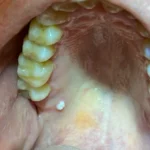

Feridas, caroços, manchas escuras, vermelhas ou brancas e inchaços. Sabemos o quanto isso pode causar medo e incômodo. Portanto, conte com os mais renomados profissionais de Goiânia para diagnosticar e cuidar do seu caso.

Caso esses sinais forem persistentes por mais de 15 dias, estamos aqui para te ajudar!

Uma das atuações mais importantes da estomatologia está na prevenção e no diagnóstico

precoce de câncer de boca. Sintomas como lesões persistentes, inchaços,

úlceras e manchas incomuns podem ser indicativos de condições

patológicas que requerem avaliação urgente.

Diagnóstico de Lesões Bucais:

Realizamos diagnósticos precisos de lesões bucais, como: feridas, caroços, tumorações, inchaços, placas e manchas com alterações na cor da mucosa bucal além de diagnóstico de lesões intra-ósseas detectadas em exames de imagens como cistos e tumores.